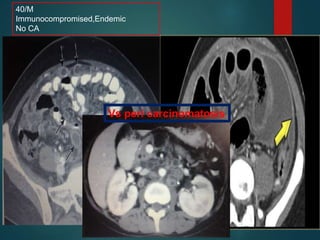

40/M

Immunocompromised,Endemic

No CA

Vs peri carcinomatosis

Peritonitis.. Tuberculous

• Produce very thick ascites, that can be

loculated in distribution… can present as a

cystic lesion.

• Peritoneum Thickening .. Minimal,smooth

• Increased density of the mesenteric fat and

High density ascities.

• Lymphadenopathy…

centrally..low attenuation